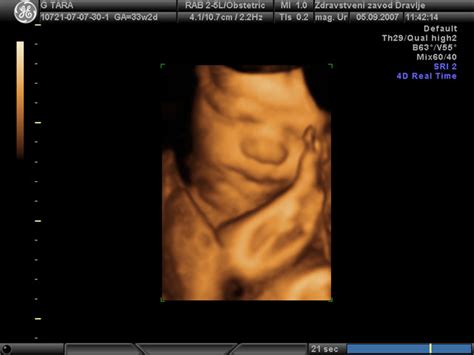

Sodoben ultrazvok (UZ) igra ključno vlogo pri zgodnjem odkrivanju možnih nepravilnosti v razvoju ploda, vključno s tistimi, ki bi lahko vodile do vodenoglavosti. Med nosečnostjo se izvajajo različni UZ pregledi, ki omogočajo spremljanje rasti in razvoja ploda.

- Morfologija ploda: Ta podrobnejši ultrazvočni pregled, ki se izvede med 18. in 22. tednom nosečnosti, omogoča natančno oceno anatomije ploda. Med morfologijo se lahko prikažejo nepravilnosti v razvoju možganov, kot so povečani možganski ventrikli, ki so lahko prvi znak potencialne vodenoglavosti. Poudarjen pleksus horoideus ali povečani lateralni ventrikli so pogosto razlog za nadaljnje spremljanje. Vendar pa je pomembno poudariti, da ti znaki sami po sebi ne pomenijo nujno vodenoglavosti, temveč zahtevajo natančnejše spremljanje.

- Dodatni UZ pregledi: V primerih, ko obstaja sum na nepravilnosti, ginekolog lahko naroči dodatne ultrazvočne preglede v poznejših fazah nosečnosti, pogosto med 30. in 32. tednom, da bi spremljali razvoj možganov in morebitno povečanje ventriklov. Ti pregledi omogočajo natančnejšo oceno stanja in načrtovanje nadaljnjih ukrepov.